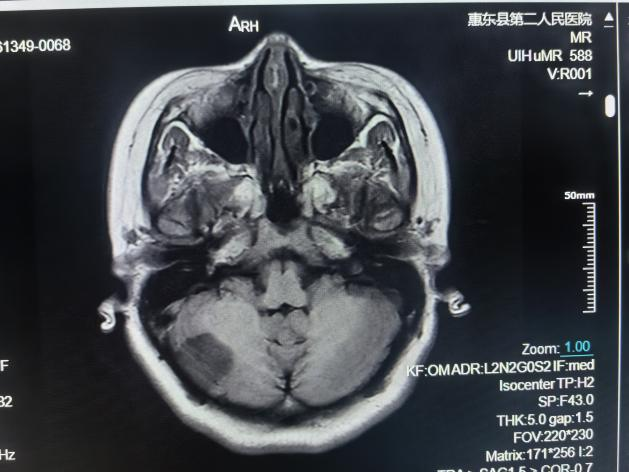

颅脑MRI检查

①先天性颅脑发育异常:包括器官源性畸形和组织源性畸形,MRI可确诊;②脑积水;③脑萎缩;④卒中及脑缺氧:脑梗塞和脑出血等;⑤脑血管疾病:高磁场的MR通过血管成像(MRA)技术显示;⑥颅内肿瘤和囊肿;⑦颅脑外伤;⑧颅内感染和其他炎性病变;⑨脑白质病。